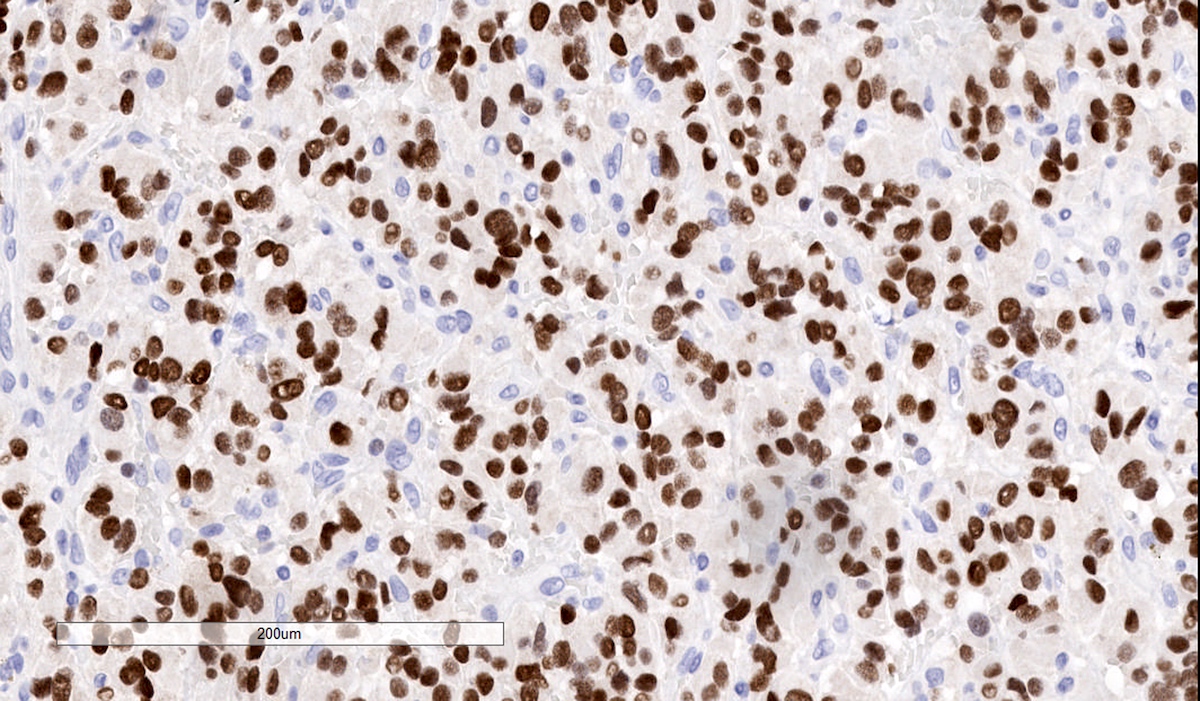

Positive stains

- INSM1 (diffuse nuclear) (Am J Surg Pathol 2018;42:665)

- S100 may be diffusely positive (J BUON 2018;23:1540)

- GATA3 (diffuse nuclear) (Hum Pathol 2020;103:72, Am J Surg Pathol 2014;38:13, J Clin Med 2018;7:280)

- Tyrosine hydroxylase (critical enzyme required for catecholamine synthesis; usually diffuse and strong in sympathetic paragangliomas, may be weak or focal in parasympathetic tumors) (Hum Pathol 2020;103:72)

- Sustentacular cells: S100, GFAP and SOX10 (Hum Pathol 2020;103:72)

- IHC surrogate markers for germline mutations:

- SDHB or SDHA expression loss: germline SDHx mutations (Lancet Oncol 2009;10:764)

- FH expression loss: germline FH mutation (HLRCC) (Hum Pathol 2018;71:47)

- Carbonic anhydrase IX (CAIX) expression: 80% of VHL mutation (Mod Pathol 2020;33:57)

- Inhibin alpha: any hypoxic pathway disease (SDHx, VHL, etc.) (Am J Surg Pathol 2021;45:1264)

- Reticulin highlights the nesting pattern (Int J Gynecol Pathol 1991;10:203, Exp Toxicol Pathol 2013;65:631)

Contributed by Luvy Delfin, M.D. and Sylvia L. Asa, M.D., Ph.D.